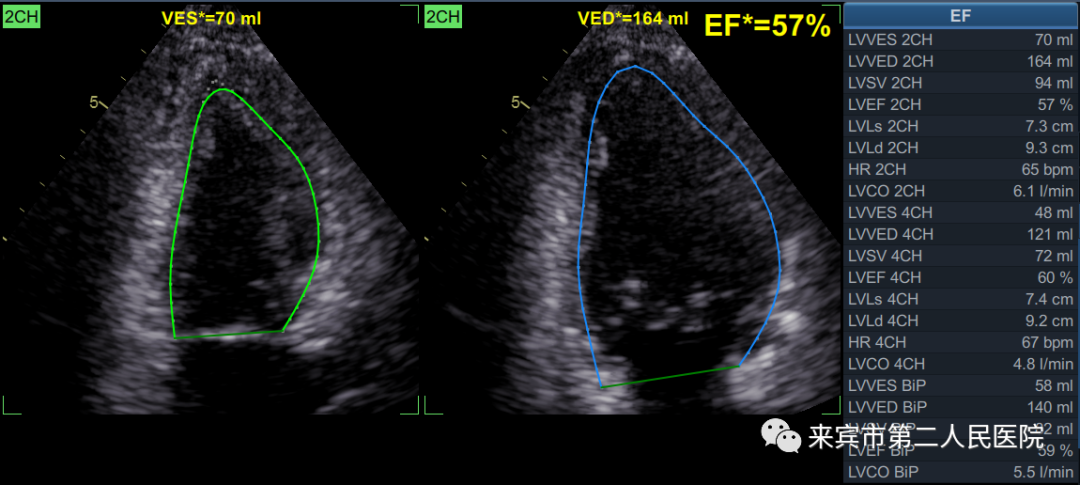

一、彩超在心脏检查中的应用:

心脏彩超又称超声心动图,心脏彩超相当于是医生的透视眼,医生可以透过人体的皮肉和骨骼,看到心脏有哪些结构,心脏大小、心脏如何搏动、心内血液流动的速度和方向。它最大的特点在于能够清晰地动态显示心脏的形态结构及功能,具有无创、方便、无辐射、连续、应用范围广的特点,对很多疾病的诊断具有确诊的价值,最适合检查一些心脏形态结构发生改变的疾病,例如先天性心脏病等。

3.自动心肌功能成像